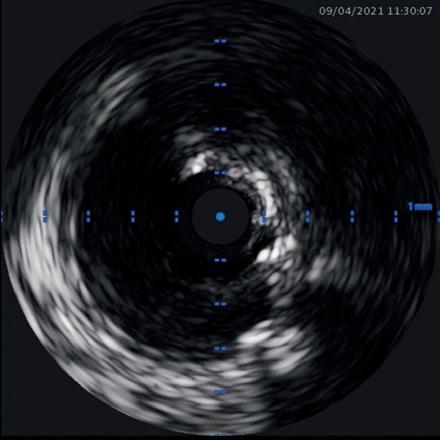

Intracoronary imaging

Among the major changes to the latest version of the guidelines is a new emphasis intravascular imaging. When performing revascularisation via PCI, intracoronary imaging—in the form of intravascular ultrasound (IVUS) or optical coherence tomography (OCT) —is deemed as being helpful to guide interventions and enhance results, especially in complex scenarios including left main disease, bifurcations, or long lesions.

on a multitude of randomised controlled trials showing consistent substantial clinical benefit,” said Lorenz Räber (Bern University Hospital, Bern, Switzerland), highlighting the importance of this new recommendation to Cardiovascular News. “Europe is lagging behind, as many believe angio is enough, so the upgrade is expected to fuel the use of imaging for complex lesions. Currently, there is no other technical refinement of PCI that reportedly improves clinical outcomes to the degree observed with intracoronary imaging.”

“Meta-analysis of randomised clinical trials had already shown that intracoronary image guidance of PCI improves patient outcomes and saves lives,” said Javier Escaned (Hospital Clinico San Carlos, Madrid, Spain). “But the IA recommendation for IVUS in the updated ESC guidelines is crucial, as it reflects expert consensus based on a definite body of evidence supporting the positive impact of IVUS, specifically for patients with anatomically complex lesions treated with PCI.”